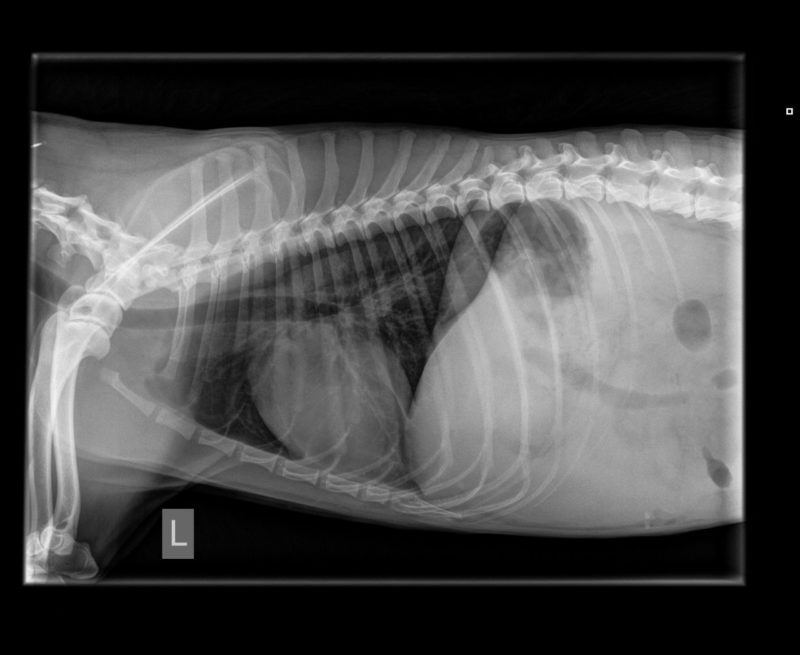

Als erste Diagnostik wurde der Hündin Blut abgenommen, um einen Blutstatus (u.a. rote und weiße Blutkörperchen, Hämatokrit, etc.) zu erstellen. In der Zwischenzeit wurde ein Röntgenbild des Abdomens erstellt. Auf dem Röntgenbild war eine hochgradige Aszites (Flüssigkeitsansammlung in der Bauchhöhle) zu sehen, daher war das Abdomen nicht wirklich beurteilbar und aufgrund dessen wurde ein Ultraschall angesetzt. Hier zeigte sich, dass die Blase geringgradig Urinsediment aufwies, die Nieren sowie die Milz waren makroskopisch unauffällig, die Leber war deutlich verkleinert und inhomogen, die Gallenblasenwand erschien geringgradig verdickt. Die Dünndarmschlingen waren etwas hyperechogen und zeigten eine verdickte Mukosa, bei erhaltener Darmschichtung. Es erfolgte eine ultraschallgeführte Punktion der Bauchhöhle, um ein Probe der Bauchhöhlenflüssigkeit zu bekommen. Diese war makroskopisch wie Wasser ohne Hinweise auf Blutbeimengungen oder einem besonderem Geruch.